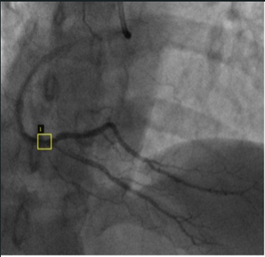

Before employing the images in the YOLO model, vascular occlusions in each XCA image were first identified, and the locations of stenosis were labeled by an expert cardiologist. This crucial step ensured that the dataset was accurate and aligned with clinical standards. For the labeling process, an online annotation tool called VIA (VGG Image Annotator) was utilized [27]. VIA allowed for precise annotation of the stenotic regions, using the existing data values in the supplied dataset to guide the labeling process while preserving the expert’s original decisions without alteration. Each labeled image was then saved in a JSON file format, containing detailed information about the occlusion locations and corresponding metadata. Figure 4 illustrates examples of the labeled images, demonstrating how the stenotic regions were highlighted for further processing. This thorough labeling process was essential for training the YOLO model to accurately detect and classify coronary artery stenosis.

Figure 4. Sample labeled images